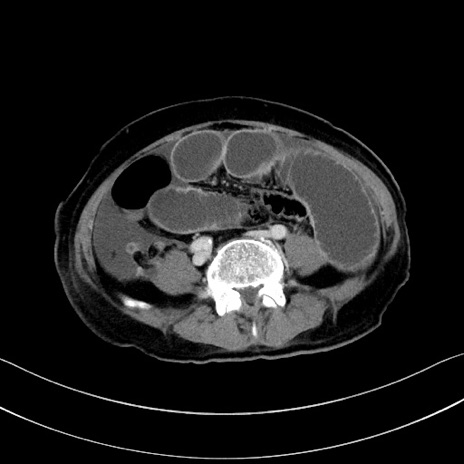

症例28(横断像)

【症例】60歳代男性

【主訴】嘔吐

【現病歴】胃癌にて胃全摘後。食思不振が悪化し、夜中に嘔吐することがある。

【既往歴】胃癌、胃全摘、脾摘、胆摘後

【データ】WBC 5900、CRP 10.56